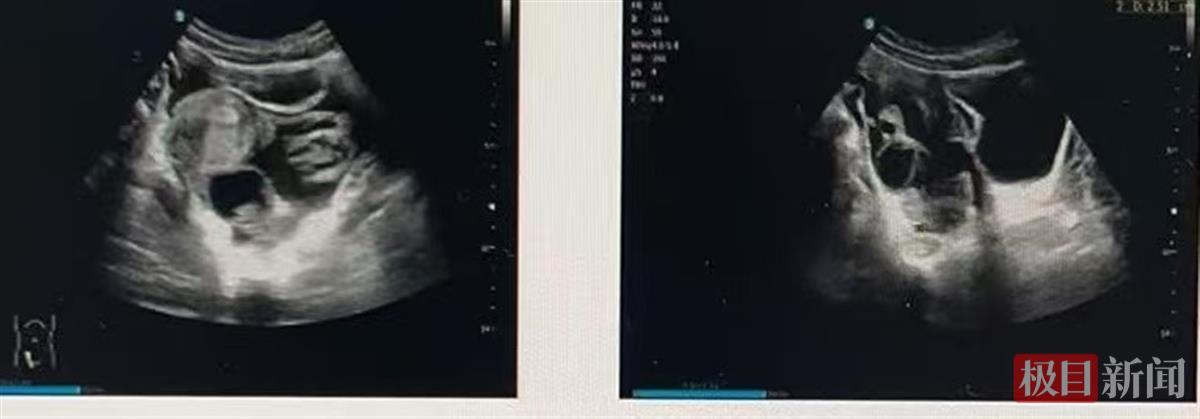

小孙B超检查图

武汉市第四医院妇产科汪莹医生接诊后详细询问了小孙的情况,并进行了相关检查。B超检查提示小孙右侧卵巢旁有不均匀回声,并存在盆腔积液。结合检查结果及临床表现,小孙被诊断为黄体破裂。住院后,小孙接受了止血、预防感染等治疗。